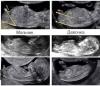

Как то знаю что по половому бугорку определяют,посмотрите ☺️

По половому бугорку девочка

@luchik122, там только ноги видно и всё. Полового бугорка нет. Поэтому оценить кто прав а кто нет, увы не возможно. Вот у автора поста четко видно девочка. Прям ну очень хороший снимок узи, что редко. У меня не так явно было видно

Девочка